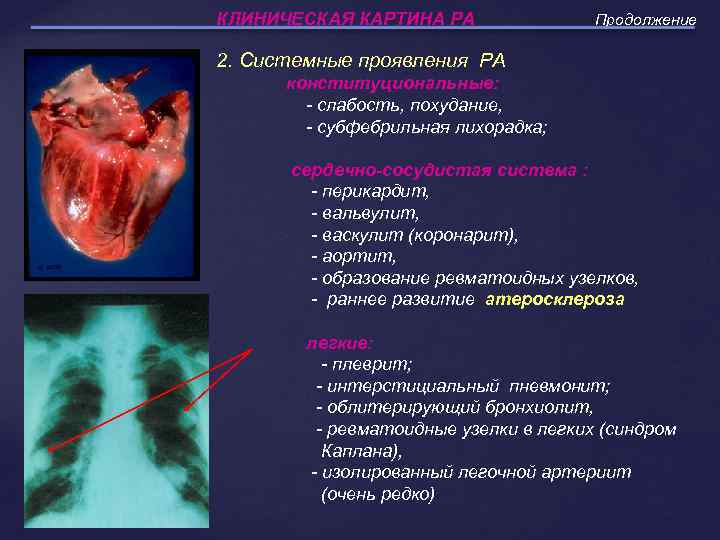

КЛИНИЧЕСКАЯ КАРТИНА РА Продолжение 2. Системные проявления РА конституциональные: - слабость, похудание, - субфебрильная лихорадка; сердечно-сосудистая система : - перикардит, - вальвулит, - васкулит (коронарит), - аортит, - образование ревматоидных узелков, - раннее развитие атеросклероза легкие: - плеврит; - интерстициальный пневмонит; - облитерирующий бронхиолит, - ревматоидные узелки в легких (синдром Каплана), - изолированный легочной артериит (очень редко)

КЛИНИЧЕСКАЯ КАРТИНА РА Продолжение 2. Системные проявления РА конституциональные: - слабость, похудание, - субфебрильная лихорадка; сердечно-сосудистая система : - перикардит, - вальвулит, - васкулит (коронарит), - аортит, - образование ревматоидных узелков, - раннее развитие атеросклероза легкие: - плеврит; - интерстициальный пневмонит; - облитерирующий бронхиолит, - ревматоидные узелки в легких (синдром Каплана), - изолированный легочной артериит (очень редко)